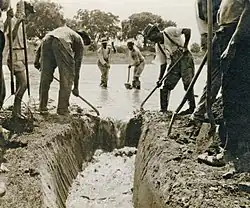

Existem outros métodos destinados a reduzir o número de picadas de mosquito e abrandar a disseminação da malária. Uma vez que a larva do mosquito se desenvolve em águas estagnadas, drenar essa água ou acrescentar-lhe substâncias que diminuem o seu desenvolvimento é uma técnica eficaz nalgumas regiões.[65] No entanto, não há qualquer evidência que os aparelhos eletrónicos repelentes de insetos através de ultrassons sejam minimamente eficazes.[66]

O primeiro pesticida usado para a vaporização residual interior foi o DDT.[132] Embora inicialmente fosse usado em exclusivo para combater a malária, rapidamente começou a ser usado também na agricultura. Com o decorrer do tempo, o produto passou a ser usado principalmente para o controlo de pragas em larga escala, o que provocou a resistência dos mosquitos ao pesticida em inúmeras regiões. Durante a década de 1960, aumentou a consciencialização pública do impacto negativo do seu uso indiscriminado, o que levaria na década seguinte à interdição do DDT na agricultura em vários países.[57] Antes do DDT, nas áreas tropicais como o Brasil ou o Egito, a malária era eliminada ou controlada através da remoção ou envenenamento dos habitats de reprodução do mosquito ou dos habitats aquíferos das larvas ao aplicar, por exemplo, o composto altamente tóxico Verde de Paris em águas estagnadas.[133]

A malária já foi erradicada ou bastante reduzida em determinadas regiões. A doença já foi comum nos Estados Unidos e na Europa do sul, mas as iniciativas de controlo de vectores em conjunto com a monitorização e tratamento de indivíduos infetados, proporcionaram a sua erradicação. Para tal contribuíram vários factores: a drenagem de terrenos alagados para agricultura, diversas alterações nas práticas de gestão de recursos hídricos, generalização do saneamento e uso de janelas de vidro e redes mosquiteiras nas habitações.[150] Os mesmos métodos permitiram erradicar a malária da maior parte dos Estados Unidos no início do século XX, restando apenas nalguns focos no Sul, tendo sido erradicada por completo na década de 1950 com recurso a DDT.[151] No Suriname, a doença foi erradicada da capital e regiões costeiras em 1955 através de um programa que consistia em três medidas: controlo de vectores através do uso de DDT e vaporização residual; recolha regular de amostras de sangue da população para identificar casos da doença; e tratamento com quimioterapia para todos os infetados.[152] O Butão tem implementada uma estratégia agressiva de erradicação, tendo conseguido entre 1994 e 2010 uma redução de 98,7% dos casos confirmados através de microscopia. Estas metas foram conseguidas com recurso a técnicas de controlo de vectores, como a vaporização residual em áreas de risco e através da distribuição de redes tratadas com pesticidas, auxiliadas pelo desenvolvimento económico e melhoria no acesso a serviços de saúde.[153]